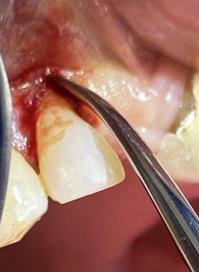

Sindesmotomía con un periostótomo de molt # 9, posteriormente se realizó la luxación con un elevador recto, buscando el punto de apoyo, seguido se efectuó la prensión con el fórceps 150 en el diente con sumo cuidado de no tocar la encía colocándolo hasta el cuello dental, haciendo movimientos de lateralidad y rotación hasta lograr la dilatación del alveolo, y finalmente la tracción del órgano dentario, observando que la raíz este integra, y que estructuras alrededor estén conservadas, de la misma forma se revisó el alveolo en busca de la presencia de granulomas o espículas óseas, una vez ya revisado se procedió al curetaje, con una cucharilla de lucas, se introdujo y se dio paso al retiro del exudado purulento, se realizó irrigación del alveolo con solución fisiológica, una vez limpio se realizó una sutura simple con sutura nylon, seda # 3/0 en el medio del alveolo con la finalidad de aproximar rebordes, evitar su contaminación por el ingreso de comida, además generar una mejor cicatrización en una zona estética , finalmente se aplicó presión por medio de una gasa que mordió el paciente por un lapso de 30 minutos, para contribuir con una hemostasia adecuada.

Figura 8. Irrigación del alveolo con solución fisiológica y sutura simple en la mitad del alveolo.

Elaboración: Los autores.